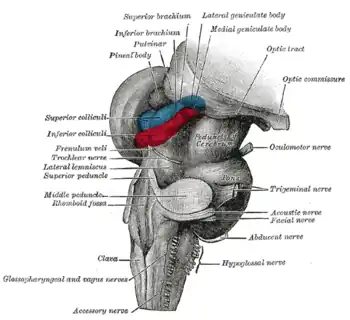

El cuerpo pineal está etiquetado en estas imágenes.

Glándula pineal. Tronco encefálico. Vista posterior.

Tronco encefálico. Vista posterior.